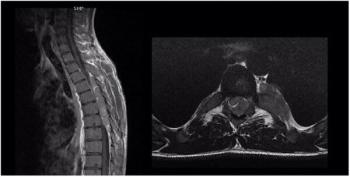

25-year-old man presents with progressive lower extremity weakness.